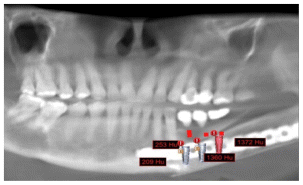

The patient after surgery continued under observation and could not continue with her treatment due to the Covid epidemic, resuming the treatment on 03/02/2014 for the reassessment by CT the new bone formed in the area of surgery was observed by two programs Blues Sky Bio and Mimics of Materialise the values in Hounsfield units were determined in each of the CT slices at the sites planned for the placement of three implants, the values ranged from 209 U. Hounsfield to 1372 U. Hounsfield (Figs, 15,16,17,18).